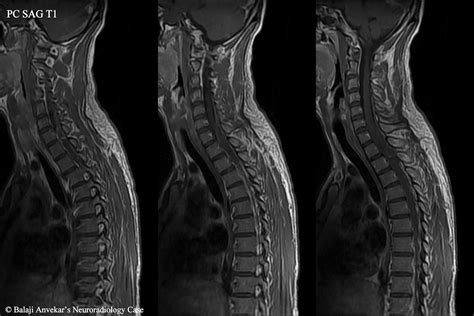

• MRI Cervical Spine without Contrast